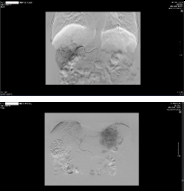

• Điều trị tiếp theo: TACE lần 3

| TACE lần 3 | Sau 1 tháng |

Hình 4. Quá trình nút mạch khối u gan hai bên lần 3 |

Hình 5. Kết quả chụp MRI gan-mật sau TACE lần 3 một tháng, khối u gan hai bên vẫn tăng sinh mạch nhiều, có nốt mới cạnh khối cũ, huyết khối nhánh phải tĩnh mạch cửa |

| | AFP: 1432ng/mL AFP-L3: 43% Pivka-II: 6023mAU/mL |

Bảng 2. Đánh giá đáp ứng điều trị sau TACE lần 3 chất chỉ điểm u tiếp tục tăng

=> Bệnh nhân được chuyển sang điều trị thuốc đích Sorafenib 800mg/ngày